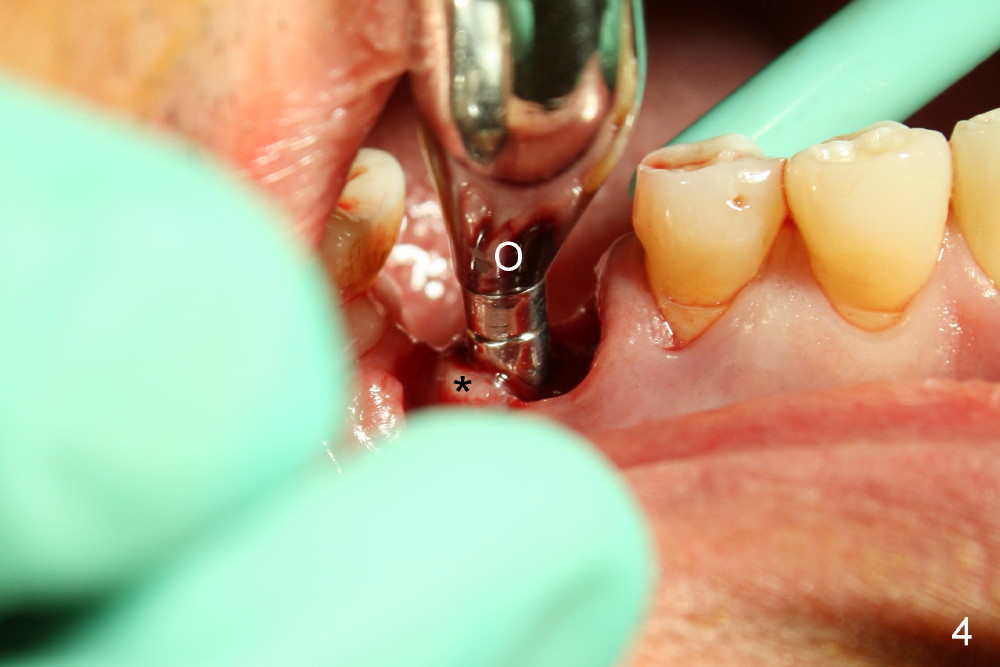

There are three sockets: mesial (M), distobuccal (DB) and distolingual (DL) following extraction. It is reasonable to place a large implant in the mesial socket with intention to push the septum and furcal gingiva (*) distally.

A series of osteotomes (Bone Scalpel, Bone Blade, and Round Tapered, Tatum Surgical) are used to displace the septum and furcal gingiva (* in Fig.4; O: 5 mm RT).